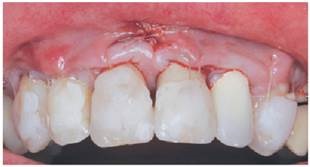

La zona en relación a las recesiones a tratar fue anestesiada con articaína 4% (Septanest®), y luego las superficies radiculares fueron pulidas con cureta Gracey Mini-five 1-2 (Hu-Friedy®). Posteriormente, se realizó una incisión vertical de acceso (hoja 15c Hu-Friedy®) sobre el frenillo medio superior, para lograr un acceso a ambos cuadrantes del maxilar. Esta incisión se realizó con el fin de elevar un colgajo mucoperióstico11 a nivel de encía adherida mediante un tunelizador (TKN2 Hu-Friedy®), alcanzando la zona intrasurcular de piezas 1.4 a 2.4. Posteriormente, a nivel del límite mucogingival, se comenzó a elevar un colgajo mucoso, con el fin de permitir el desplazamiento del colgajo a coronal (fig.2). Una vez eliminada la tensión del colgajo, se procedió a medir la extensión del tejido necesaria para injertar la zona receptora del lado izquierdo y así obtener un injerto libre palatino del lado izquierdo. Se obtuvo injerto libre, ya que permite conseguir un conectivo de mejor calidad y requiere de una técnica menos compleja de obtención. Luego de obtenido, se colocó cemento quirúrgico en la zona dadora, y el injerto se desepitelizó con una hoja de bisturí nueva (hoja 15c Hu-Friedy®). Para posicionar el ITC y el Mucograft® en sus respectivos sitios, se introdujo una sutura reabsorbible multifilamento 5/0 (Safil®) sobre encía adherida en distal de la recesión más distal a injertar de cada lado y se pasó por la incisión vestibular realizada sobre el frenillo medio superior. Luego, la sutura se pasó por el borde de cada injerto y se volvió realizando el camino inverso al de entrada, traccionado el injerto para luego suturarlo en distal y mesial. Una vez posicionado el ITC en la zona receptora del lado izquierdo (pd 2.1 a 2.3) y el Mucograft® en la zona receptora del lado derecho (pd 1.1 a 1.3), el colgajo se desplazó 2mm coronal al LAC, intentando llegar al nivel más coronal de la papila interproximal, fijándolo mediante sutura suspensoria. Para esta técnica de sutura y tracción coronal del colgajo, se realizó un punto simple (sutura reabsorbible multifilamento 5/0, Safil®) 2-3 mm apical al margen gingival de cada diente a tratar, abarcando el ancho del diente. Se acondicionó la cara vestibular de cada diente, en el centro de la corona, con ácido ortofosfórico al 37% por 5 segundos, se lavó con suero y se secó. La sutura fue posicionada y adherida a la cara vestibular de cada pieza con composite (Flow z350 3M®), sin utilización de adhesivo. Posteriormente, la incisión vestibular sobre el frenillo medio superior, se suturó con sutura reabsorbible multifilamento 5/0 (Safil®) (fig.3).